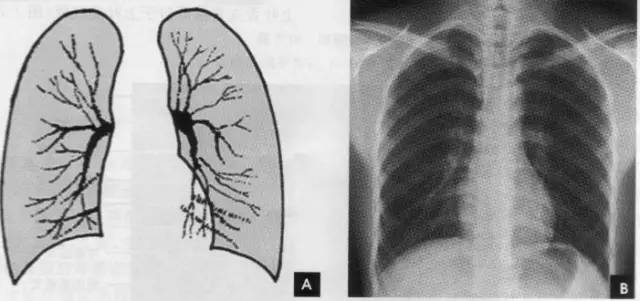

肺纹理为自肺门向肺野呈放射状分布的树枝状阴影,它主要是肺动脉的投影,肺静脉、支气管和淋巴管也参与形成。平片可显示肺纹理的多少,粗细.分布,有无扭曲、变形与移位等。肺纹理由肺门向外围延伸,逐渐变细,至肺野外带渐细小而稀少,距侧胸壁内缘约1cm范围内的肺野基本无肺纹理可见(图下图)。

为便于指明病变的部位,通常人为地将一侧肺野纵向分为三等分,即内、中、外带。又分别在两侧第2、4肋骨前端下缘划一水平线,将肺野横向分为上、中、下三个肺野。一般将第1肋圈外缘以内部分称为肺尖区,将锁骨以下至第2肋圈外缘以内部分称为锁骨下区,将最下肺靠近膈面的部分称为肺基底部(如上图)。

在胸片上不能显示各肺叶的界限,但可通过正侧位胸片上显影的叶间胸膜推断肺叶的解剖范围。右肺分为上、中、下三叶;左肺分为上、下二叶(如上图)。